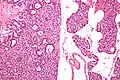

Микропрепарат аденомы паращитовидной железы.

Микропрепарат аденомы паращитовидной железы. Микропрепарат аденомы паращитовидной железы.

Микропрепарат аденомы паращитовидной железы..jpg) Микропрепарат аденомы паращитовидной железы.

Микропрепарат аденомы паращитовидной железы..jpg) Микропрепарат аденомы паращитовидной железы.

Микропрепарат аденомы паращитовидной железы..jpg) Микропрепарат аденомы паращитовидной железы.

Микропрепарат аденомы паращитовидной железы.